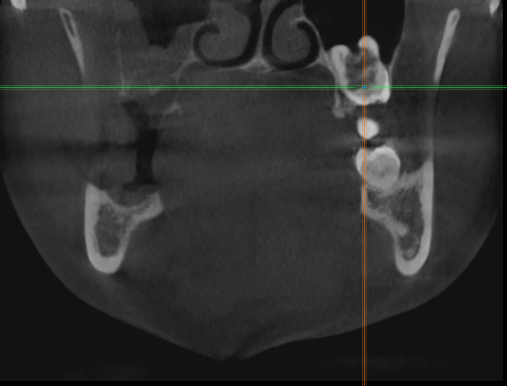

Женька Опубликовано 1 апреля, 2021 Поделиться Опубликовано 1 апреля, 2021 Значит придётся пациентке отказать... Не понимаю пока куда тут можно зслить и как. Про бш помню-знаю. Но топить нужно же не в кости 3-4 мм? Ссылка на комментарий

Женька Опубликовано 1 мая, 2021 Поделиться Опубликовано 1 мая, 2021 01.04.2021 в 13:26, red_butler сказал: заглубить с проведением ЗСЛ у все пройдет Ну что же. Пациентка согласилась на синус и имплантацию...а я надеялся что нет Только планирую пойти через открытый все-таки. Тк во-первых это можно сказать первый синус, во-вторых боюсь что при зсл я получу перфо ввиду анатомии синуса. Ссылка на комментарий

Irouil Опубликовано 1 мая, 2021 Поделиться Опубликовано 1 мая, 2021 (изменено) Вы тут с открытым синусом в 10 раз вероятнее накосячите, чем с закрытым Потому что даже если просто перфорнуть тут пазуху при ЗСЛ с очень высокой долей вероятности произойдёт чуть менее чем ничего А если начать отслаивать слизистую пазухи отдельным доступом, да еще и прямо по медиальной границе альвеолярной бухты, да еще и так высоко, да еще и планировать натолкать туда графта или еще какой-нибудь дряни... сразу ЛОРа хорошего номер ищите) Изменено 1 мая, 2021 пользователем Irouil 2 1 Ссылка на комментарий

Женька Опубликовано 2 мая, 2021 Поделиться Опубликовано 2 мая, 2021 А я думал наоборот. Открытый проще во всех смыслах Предлагаете просто зсл, губку если перфо внутрь, если нет то просто поднять пазуху и всё? без графтов чисто на сгустке? Ссылка на комментарий

Irouil Опубликовано 2 мая, 2021 Поделиться Опубликовано 2 мая, 2021 Без графтов, преп на -1-1.5 мм от высоты гребня пилотном, потом конденсация до 3.2 (или какой там у Вас диаметр вогнутого остеотома), дальше стук, по необходимости конденсинг и профайлинг крестального модуля либо реверс-препинг всей длины (в зависимости от планируемого винта) потом просто крутить 8 мм в этой ситуации на мой взгляд ничем графтить не нужно Ссылка на комментарий